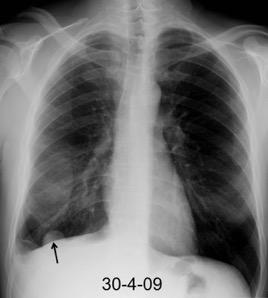

Neumonía a neumococos base izda. con derrame que aumenta.

Broncograma en lateral y en US.

(36-66% en ingresados)